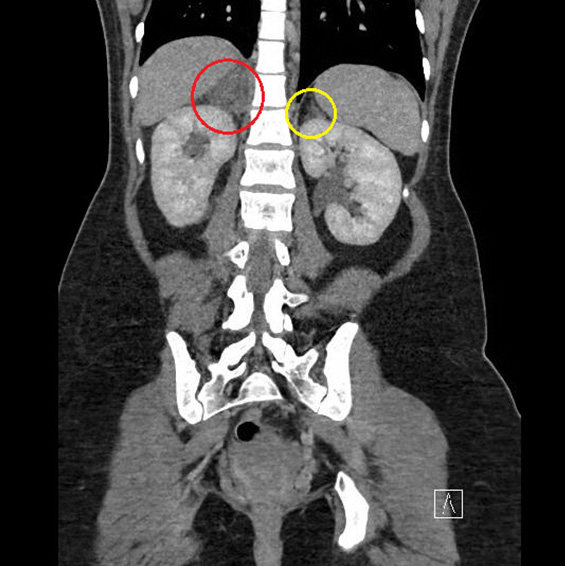

Initial imaging included a right upper quadrant ultrasound, renal ultrasound, and chest X-ray which were unremarkable. She was then transferred to our institution where antibiotics were discontinued due to no other signs of infection and negative urine culture. Due to the persistence of her abdominal pain, a computed tomography scan (CT A/P) was performed. As seen in Figure 1 and Figure 2, CT A/P showed normal appendix, but was concerning for right adrenal infarct with diffuse enlargement and hypoattenuation of the right adrenal gland with surrounding fat stranding. In light of this radiological finding, which was consistent with site of pain and acute clinical presentation, a diagnosis of right adrenal infarction was made. The patient was started on therapeutic subcutaneous low molecular weight heparin (LMWH) 70mg (1mg/kg) twice daily to prevent promulgation of adrenal infarction and prevent a similar event to contralateral adrenal gland.

Figure 2: Coronal view of right (red) and left (yellow) adrenal glands.